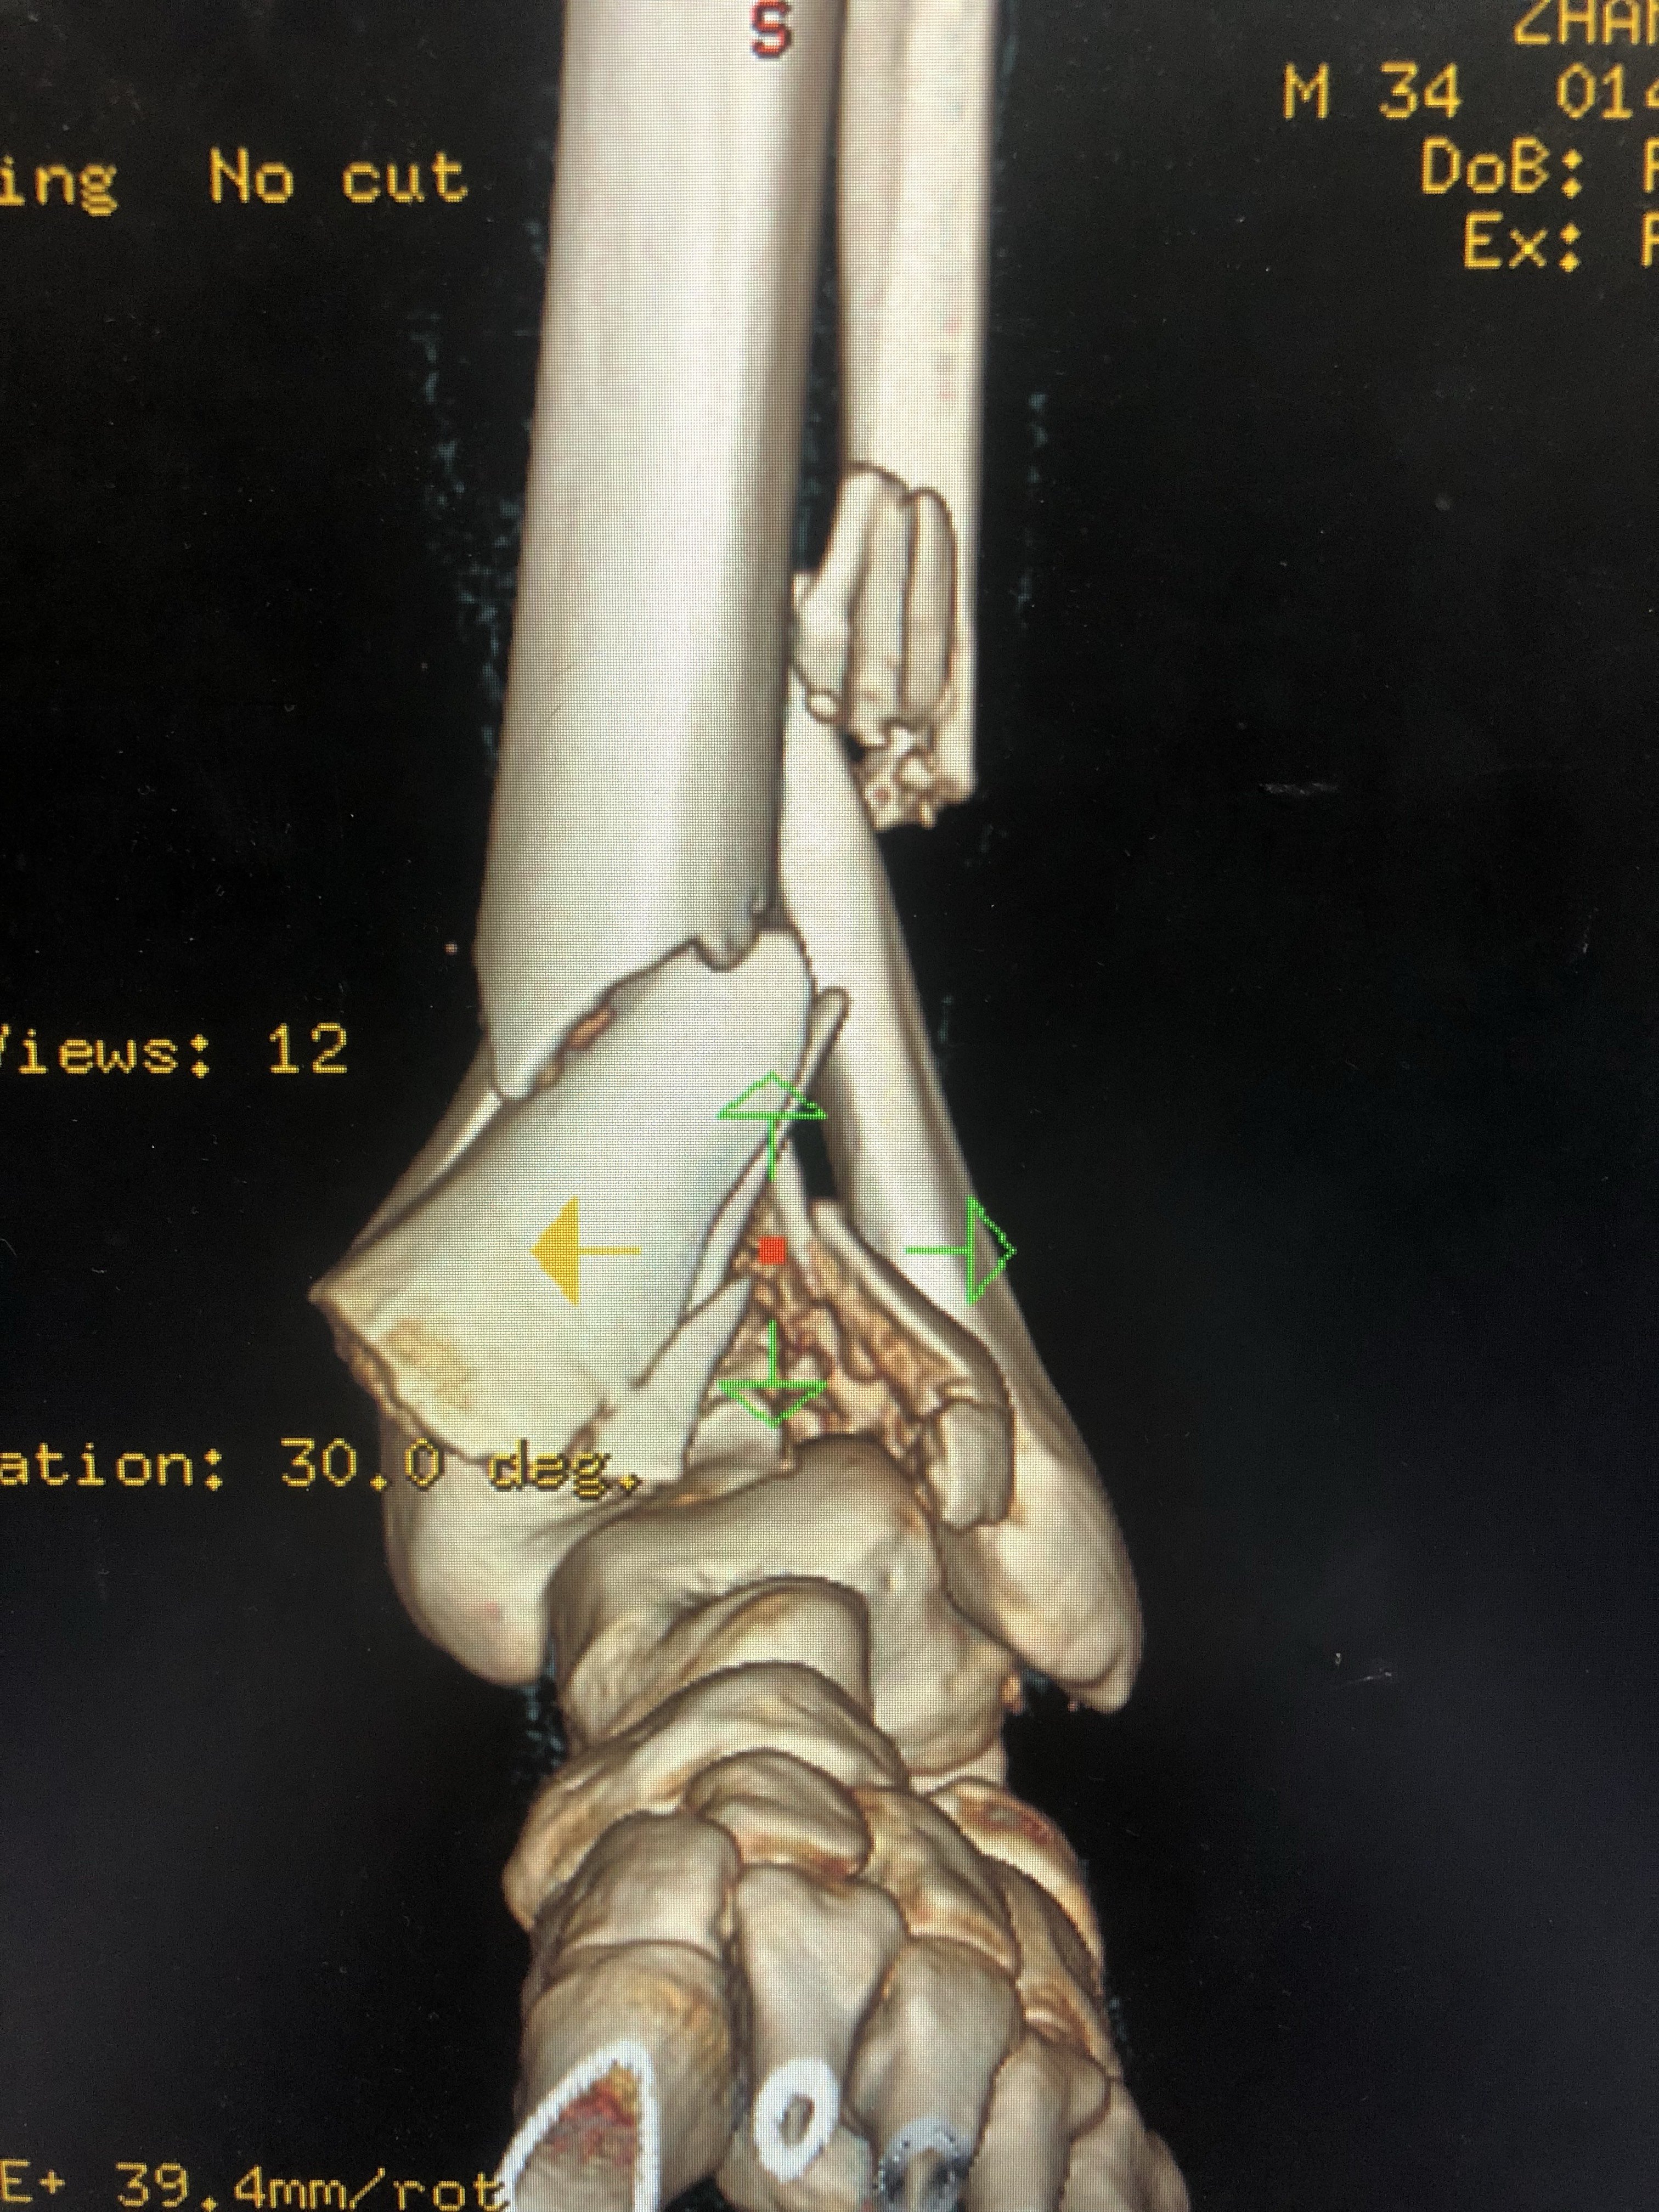

受傷した 画像所見より左腓骨遠位端骨折と診断された前 脛腓靭帯付着部の剥離骨折, 腓骨のらせん骨折および脛骨後 果の骨折からLaugeHansen分類ではSER型stageⅢであった 受傷後9日目にロッキングプレートを用いた骨接合術が施行 された左足首の骨折。 過去に足首を捻挫または骨折をして、治ってからも予防のためにサポーターを着用していませんか? サポーターを着用していると捻挫の予防になるかもしれません。しかし、時に逆効果になってしまう場合もあります。 &n交通事故の被害に遭い、脛骨骨折や腓骨骨折の怪我を。 その後、もしも後遺症が残ってしまったとしたら。 これからも長く続く治療やリハビリの生活では、 脛骨骨折・腓骨骨折から回復するために支払う治療費 怪我をしたことや後遺症が残ったことによる精神的苦痛に対する慰謝料 将来

一例严重的胫腓骨远端粉碎骨折